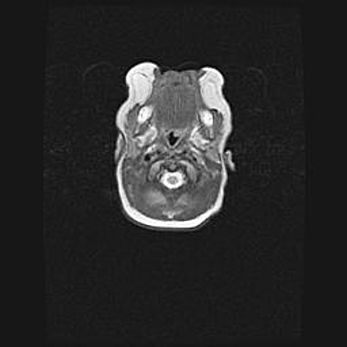

Церебральная ишемия II.

Возраст: 7 дней

Вес: 3350 г

Пол: женский

Окружность головы: 35 см

Срок гестации: 39 недель

Ишемия головного мозга – это состояние, которое развивается в ответ на кислородное голодание вследствие недостаточного мозгового кровообращения. У новорожденных она является следствием дефицита кислорода, что ведет к метаболическим расстройствам различной степени тяжести в тканях головного мозга, в том числе к развитию коагуляционных некрозов и гибели нейронов.